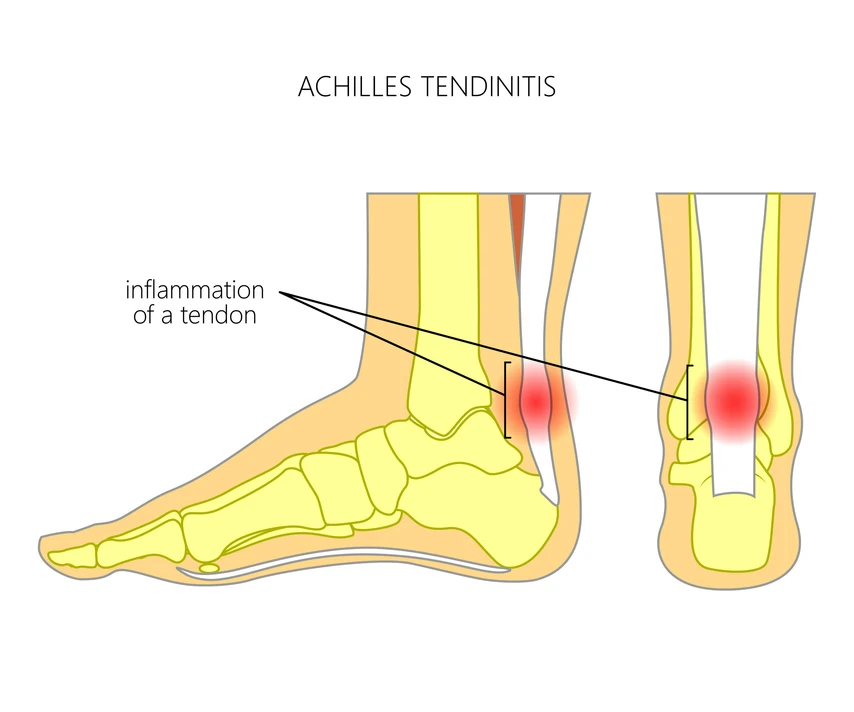

Tendons - Tendons are strong, fibrous connective tissues that attach muscles to bones, allowing the transfer of force from muscle contraction to bone movement.

Tendinitis

Inflammation of a tendon, typically due to overuse through repetitive motions, a sudden increase in activity, or acute direct injury. Symptoms include pain, tenderness, and limited movement in the affected area.